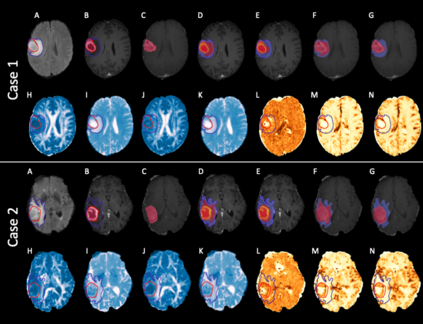

We present an Expectation-Maximization (EM) Regularized Deep Learning (EMReDL) model for the weakly supervised tumor segmentation. The proposed framework was tailored to glioblastoma, a type of malignant tumor characterized by its diffuse infiltration into the surrounding brain tissue, which poses significant challenge to treatment target and tumor burden estimation based on conventional structural MRI. Although physiological MRI can provide more specific information regarding tumor infiltration, the relatively low resolution hinders a precise full annotation. This has motivated us to develop a weakly supervised deep learning solution that exploits the partial labelled tumor regions. EMReDL contains two components: a physiological prior prediction model and EM-regularized segmentation model. The physiological prior prediction model exploits the physiological MRI by training a classifier to generate a physiological prior map. This map was passed to the segmentation model for regularization using the EM algorithm. We evaluated the model on a glioblastoma dataset with the available pre-operative multiparametric MRI and recurrence MRI. EMReDL was shown to effectively segment the infiltrated tumor from the partially labelled region of potential infiltration. The segmented core and infiltrated tumor showed high consistency with the tumor burden labelled by experts. The performance comparison showed that EMReDL achieved higher accuracy than published state-of-the-art models. On MR spectroscopy, the segmented region showed more aggressive features than other partial labelled region. The proposed model can be generalized to other segmentation tasks with partial labels, with the CNN architecture flexible in the framework.